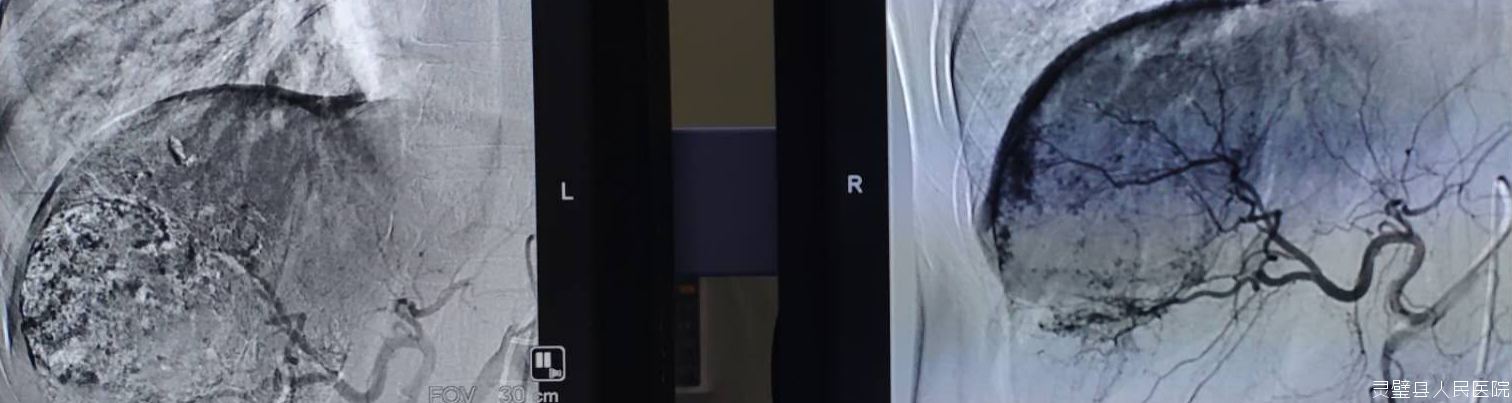

通过股动脉插管将造影剂注入肝动脉了解病变大小,将抗癌药物、栓塞剂注入肝动脉进行区域性的局部化疗治疗。介入治疗局部药物浓度较全身化疗高达数十倍,而且阻断肿瘤血供,因此双管齐下疗效好、毒性小。

目前肿瘤外科在介入治疗方面已常规开展:1.肝脏疾病的血管内介入治疗技术:肝动脉化疗栓塞术、肝动脉栓塞术,包块肝血管瘤、肝脏局灶性结节增生、肝腺瘤等;肝动脉灌注化疗术:肝癌肝动脉灌注化疗。2.肝脏疾病的非血管介入治疗技术:肝癌、胆管癌、胰腺癌、十二指肠癌等造成的梗阻性黄疸经皮穿刺胆道引流术、经皮穿刺胆囊引流术,肝脓肿穿刺引流术、肝囊肿穿刺引流硬化术。3.食管癌狭窄的支架植入术。4.下肢深静脉血栓的髂总静脉滤器植入等。